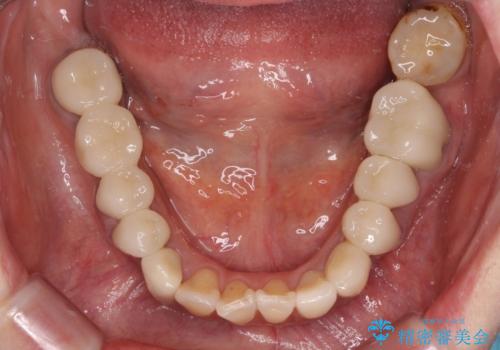

- 近医にて古いかぶせ物をセラミッククラウンにしようと治療を開始したものの、仮歯での咬み合わせが不安定とのことで、転院を希望して来院された患者様です。

骨格的に下顎骨が前方位に位置しており、上下前歯部の先端同士が接触する切端咬合でした。

このような方は咬み合わせが大きく変わると不安定となるため、まずは装着されている仮歯で咬合調整を行い、安定した咬み合わせとした後に、新しい仮歯に置き換え、その後オールセラミッククラウンにて補綴治療を行うこととしました。

仮歯で咬み合わせの調整を行ってからは、特に不安定になることもなく、非常にスムーズに治療を進めて行くことができました。

前歯奥歯ともに望ましくない力がかかりやすい咬み合わせであるため、就寝時にはマウスピースを使用するようにお伝えしております。